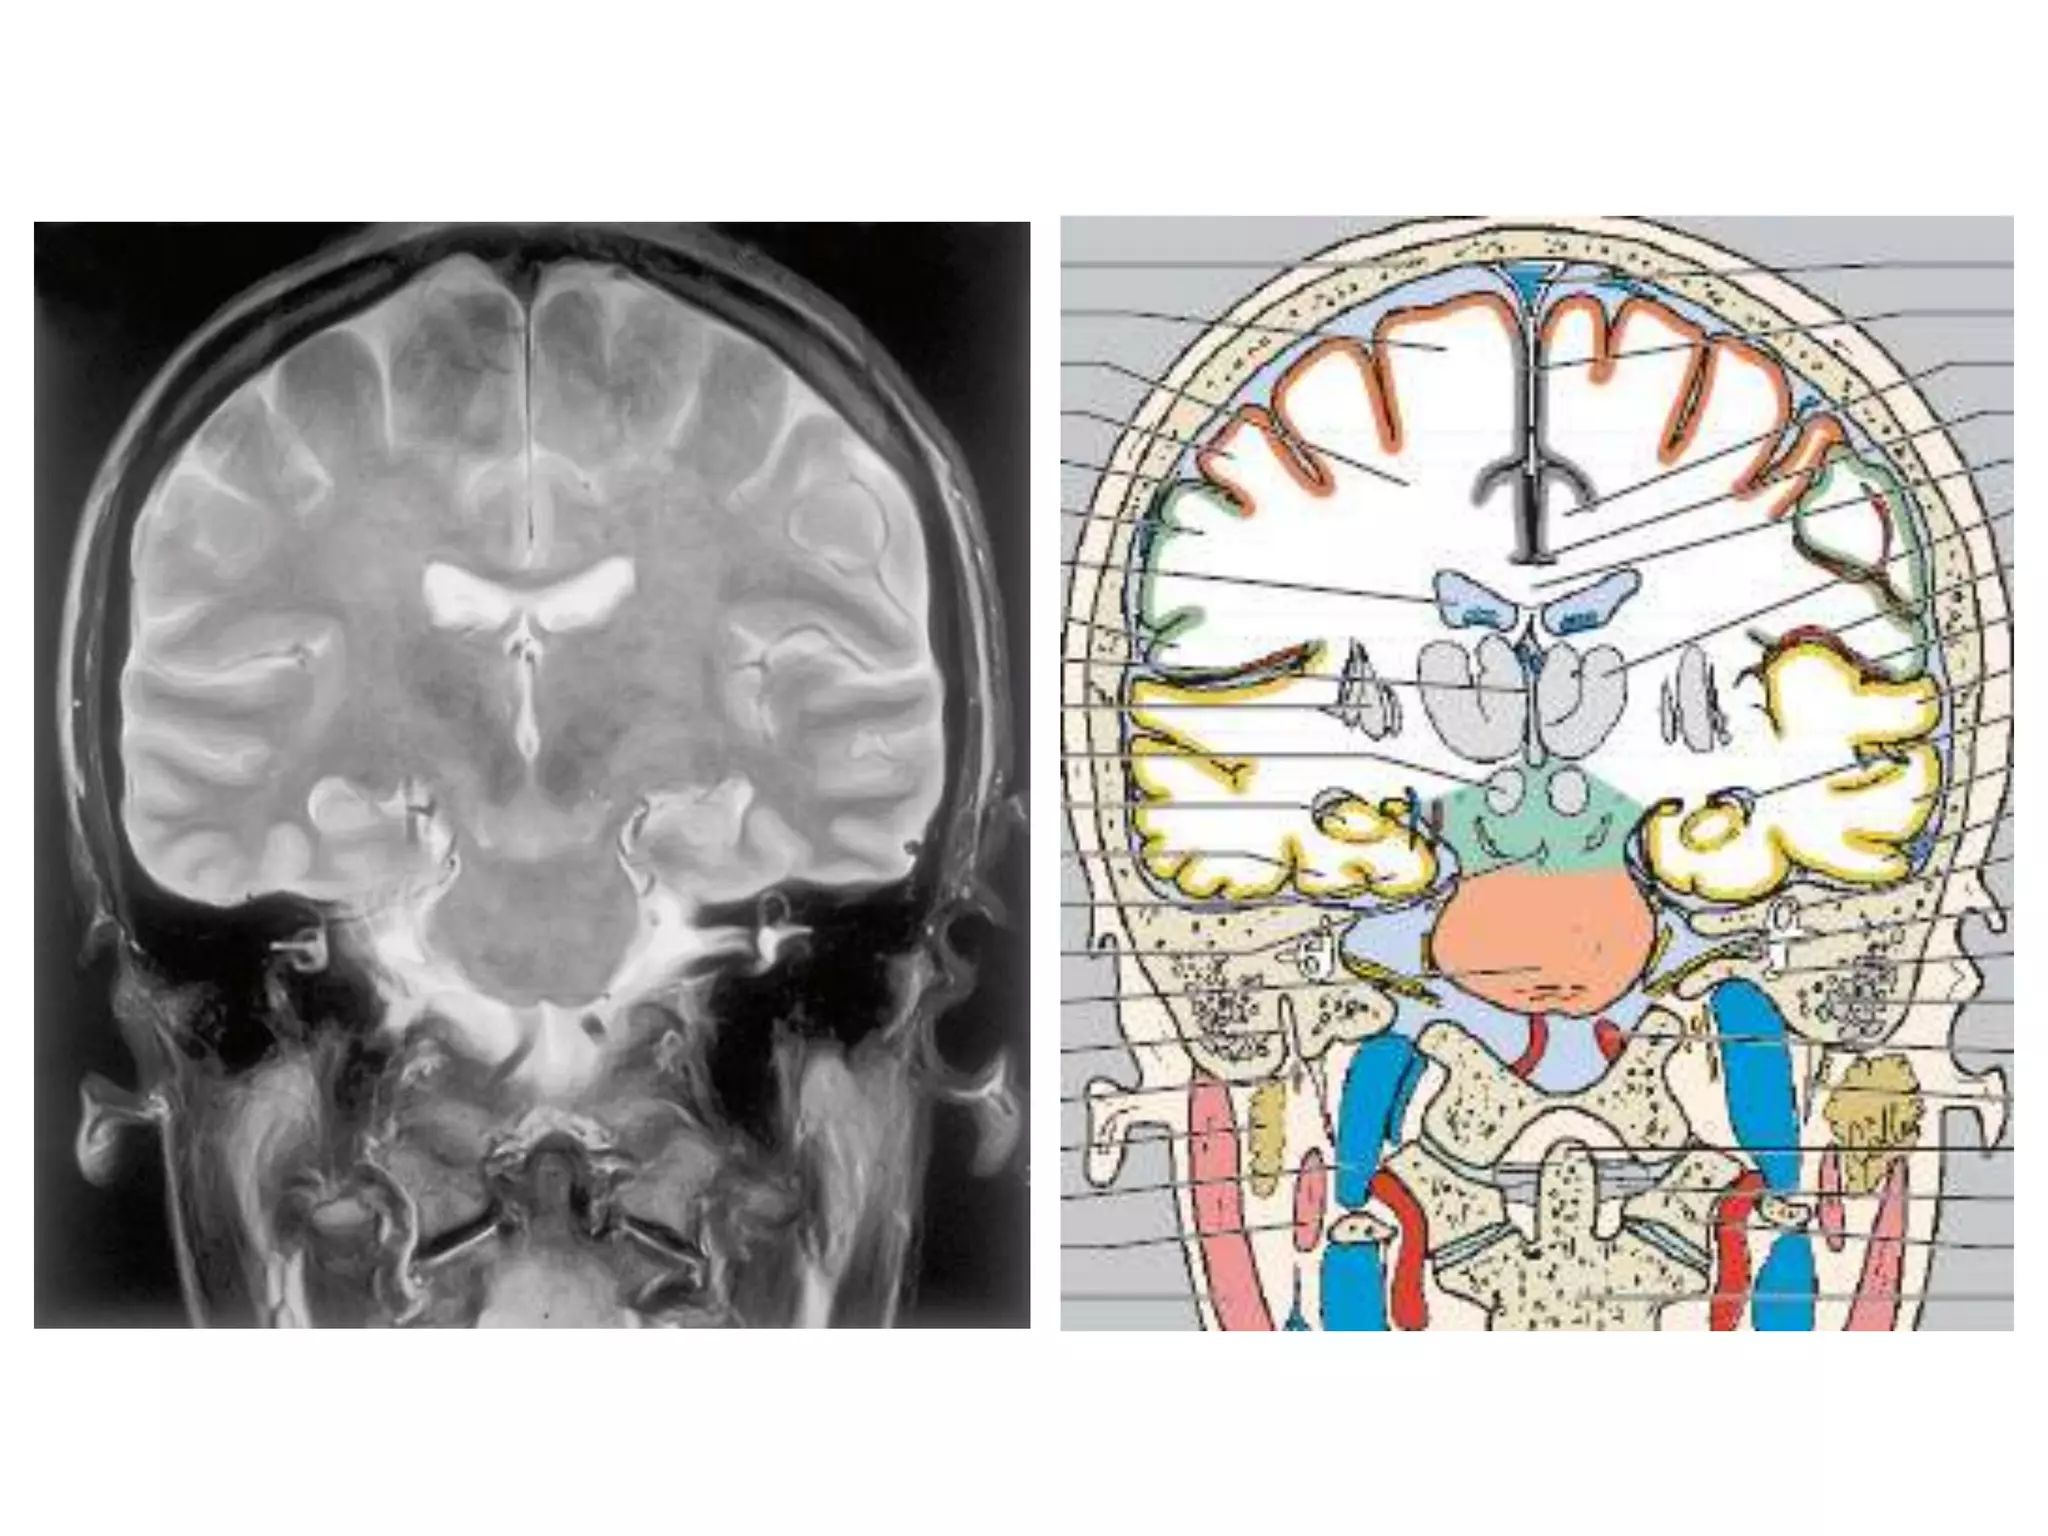

CEREBRAL HEMISPHERES

• 4 lobes are present in each hemisphere. They are

demarcated by fissures.

• Each lobe is again divided into gyri by sulci . They are

named accordingly.

• Anatomy of cerebral hemispheres and mid brain – T1 W

MRI.

• Internal grey - white matter areas – T2 W MRI.

• In Cerebral hemispheres , white matter above the level of

lateral ventricles is called centrum semiovale

CEREBRAL HEMISPHERES • 4lobes are present in each hemisphere. They are demarcated by fissures. • Each lobe is again divided into gyri by sulci . They are named accordingly. • Anatomy of cerebral hemispheres and mid brain – T1 W MRI. • Internal grey - white matter areas – T2 W MRI. • In Cerebral hemispheres , white matter above the level of lateral ventricles is called centrum semiovale